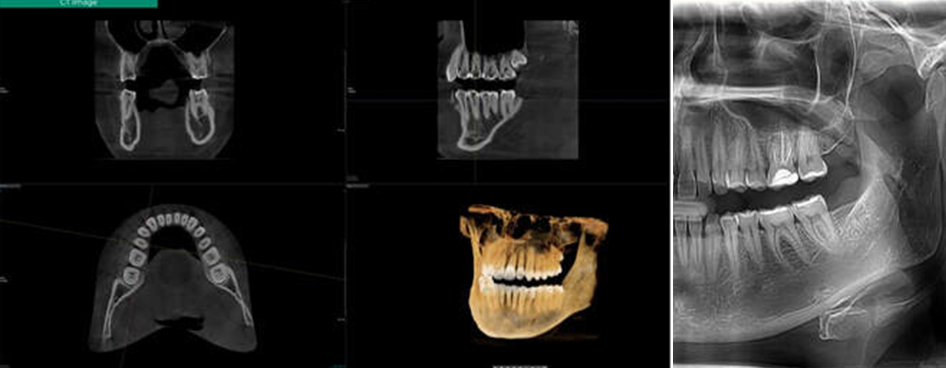

- 検査・精密診断

- レントゲンや歯科用CTを用いて、顎の骨の量や厚み、神経・血管の位置、噛み合わせの状態などを詳しく確認します。目に見えない部分まで把握することで、インプラントが可能かどうか、骨造成が必要かといった点を正確に判断します。検査結果は専門用語をできるだけ使わず、分かりやすくご説明します。

歯科用CTによる精密検査

治療前に歯科用CTで顎の骨の状態や神経・血管の位置まで立体的に確認します。見えない部分を把握したうえで計画を立てることで、無理のない治療につなげます。

シミュレーションソフトでの治療計画